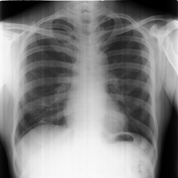

Radiographic limbs show bony ankylosis of the elbow joint, with associated hypoplasia of the ulna and proximal radius, leading to elbow flexion deformity on the left side (Figure 5). Chest x-rays show no apparent abnormalities: normal lung fields, cardiac silhouette, and bony structures (Figure 6) PA skull view show hypoplastic maxilla, prominent antigoinial notch and deviation of mandible to left side (Figure 7 &Table 1).

Figure 6 Chest radiograph showing normal lung fields, cardiac silhouette, and bony structures with no apparent abnormalities.